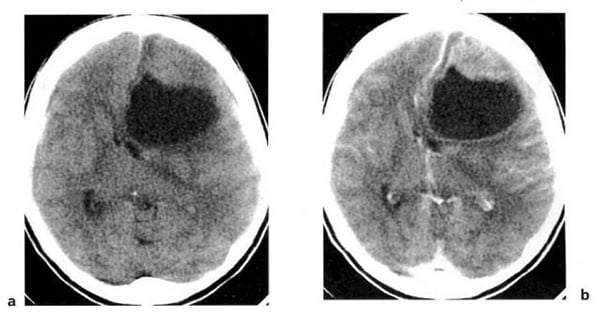

Hình 1.32. U nguyên bào đệm đa dạng. Hình ảnh trước tiêm (a) là tổn thương mật độ thấp ở hai bên đường giữa. Ở thùy trán bên trái còn có một tổn thương mật độ cao (xuất huyết). Sau tiêm (b), bắt chất cản quang mạnh, dạng viền.